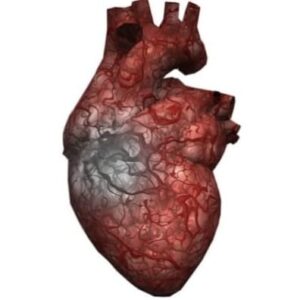

Heart diseases Types

కోరోనరీ ఆర్టరీ డిసీజ్ (CAD) – రక్తనాళాల్లో కొవ్వు చేరి బ్లాకేజ్ రావడం

హార్ట్ అటాక్ (Myocardial Infarction) – రక్త సరఫరా ఆగిపోవడం

హార్ట్ ఫెయిల్యూర్ – గుండె పూర్తిగా పని చేయకపోవడం

అరిథ్మియా (Arrhythmia) – గుండె స్పందన అసమానంగా ఉండటం

వాల్వ్ డిసీజ్ – గుండె వాల్వులు సరిగ్గా పని చేయకపోవడం

కాంజెనిటల్ హార్ట్ డిసీజ్ – పుట్టుకతో వచ్చే గుండె సమస్యలు